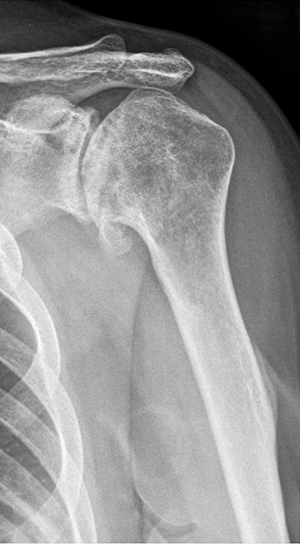

Pre-op

- 43-year-old female patient

- Primary shoulder osteoarthritis

- No cuff tear, no rotator cuff muscle atrophy

- Severe pain, poor function

- Anterior flexion 70°; external rotation 20°